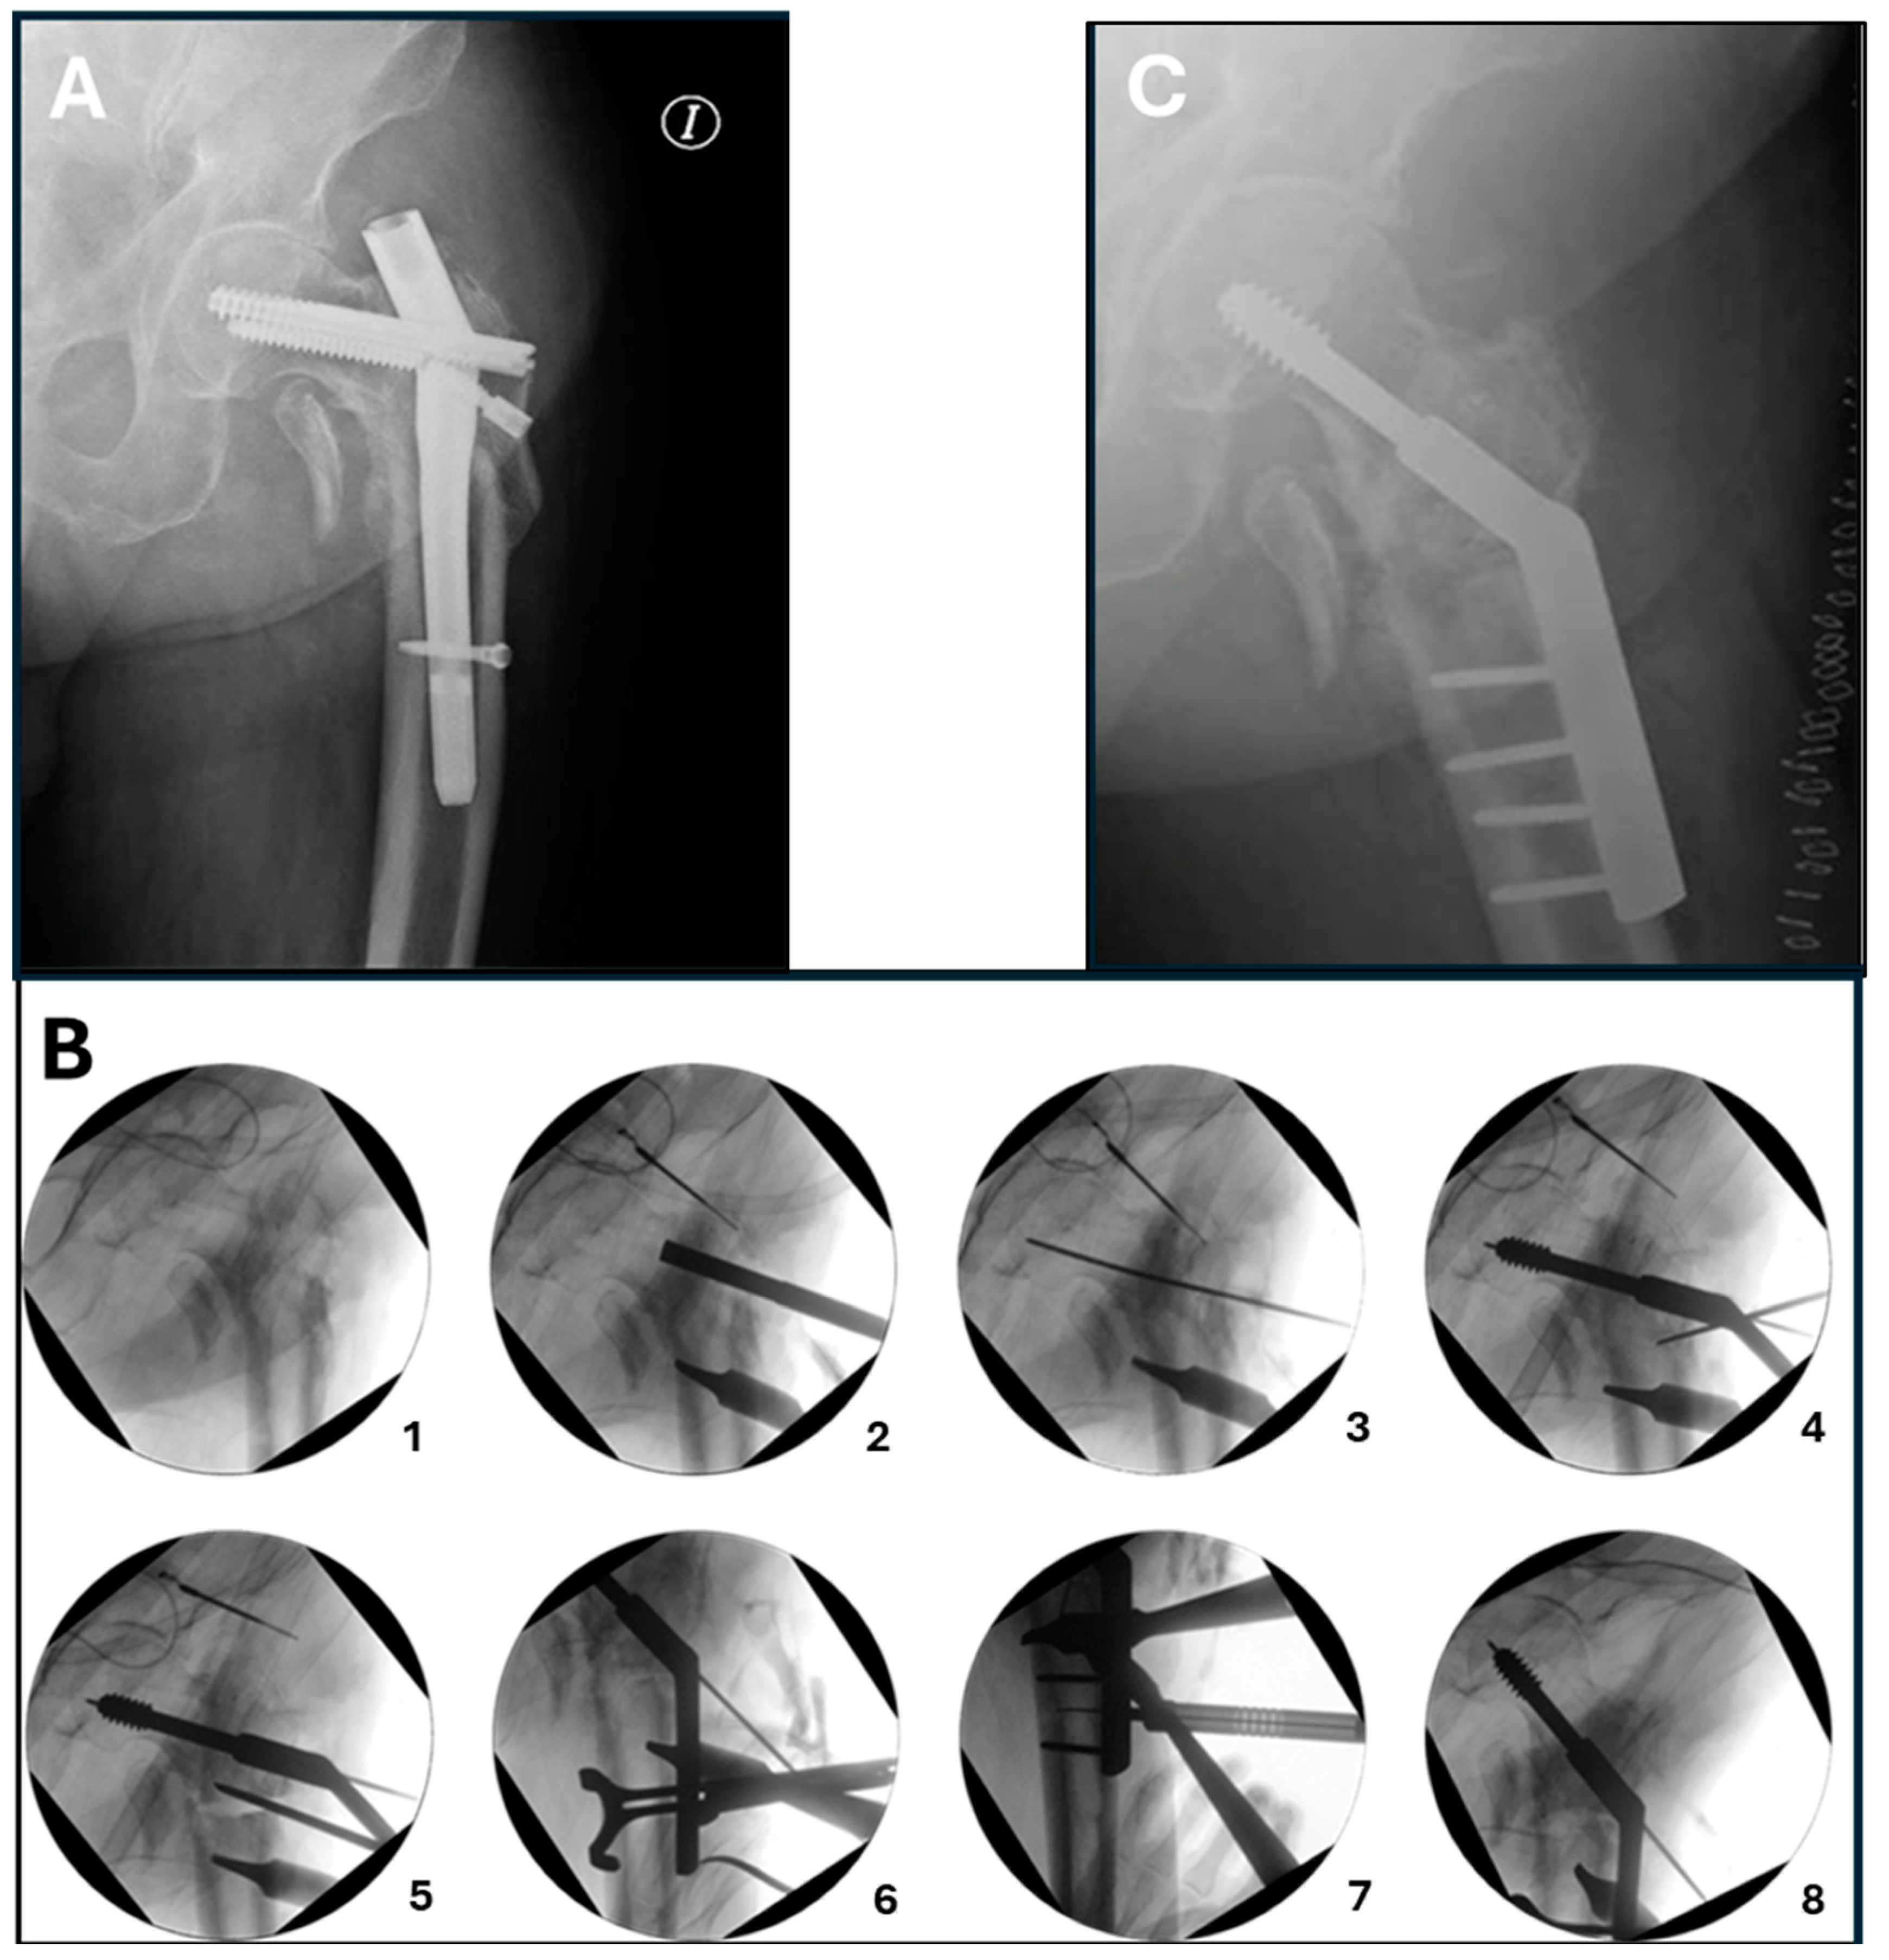

5. Surgical Procedure